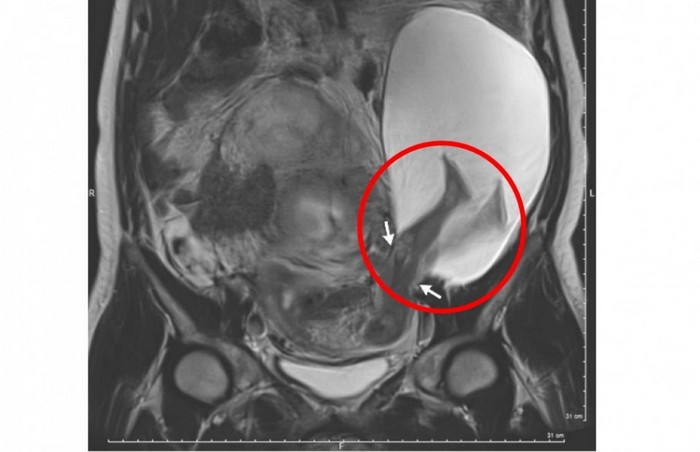

Kantung ketuban seorang wanita pecah dan kaki janin terlihat berada di luar rahim. Kelihatannya mengerikan.

Hasil foto MRI itu memperlihatkan kaki bayi keluar dari rahim ibunya. Gambar ini pun bikin heboh. Ko bisa ya?